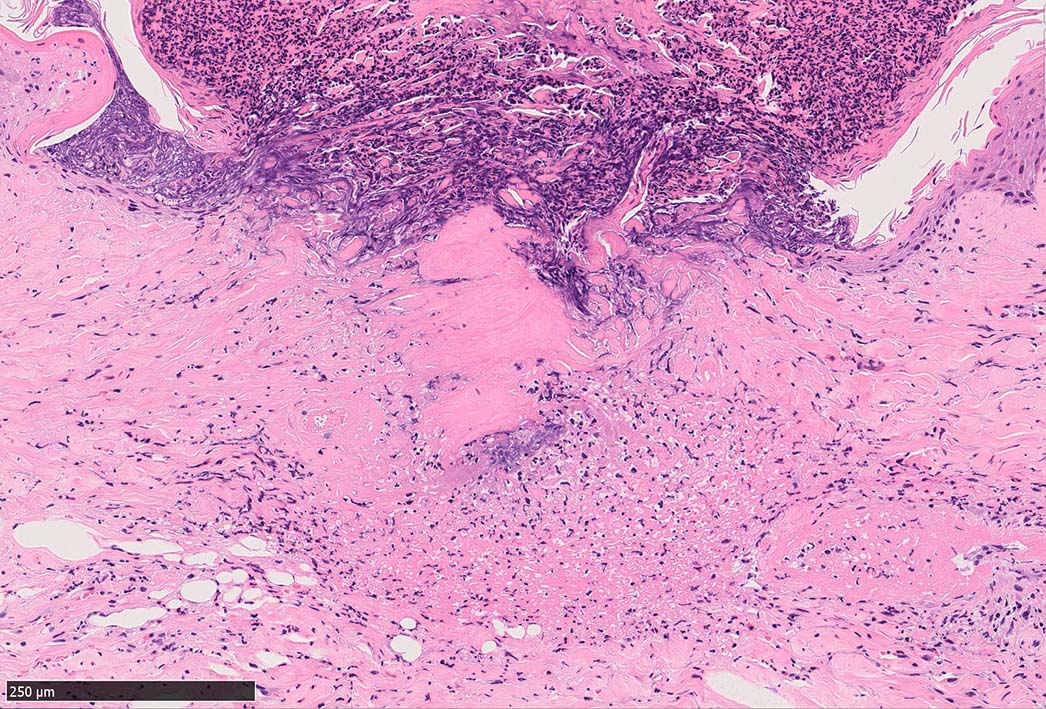

IWT-case03 マダニに咬まれた. 自分で虫体を除去したが傷がびらん化し, 発熱を来したため, 来院する.

痂皮の下に硝子様凝固物があり, 周囲には壊死組織が形成されている. 近傍の細血管には凝固物による閉塞の所見があるように見える. 連続する細血管には, fibrinoid necrosisを呈する壊死性血管炎が認められる.